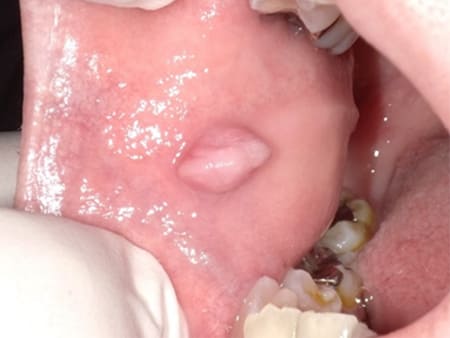

症例1 頬粘膜良性腫瘍(60歳代 女性)

頬粘膜のできものが大きくなり、違和感を認めるようになり気になり来院されました。粘膜組織の突出を認め頬粘膜良性腫瘍と診断して摘出術を施行しました。義歯のワイヤー鈎が刺激になって発生したとも考えます。